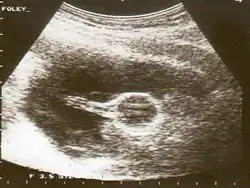

Cervical

A Foley catheter can also be used to ripen the cervix during induction of labor. When used for this purpose, the procedure is called extra-amniotic saline infusion.[9] In this procedure, the balloon is inserted behind the cervical wall and inflated, for example with 30-80 mL of saline.[9] The remaining length of the catheter is pulled slightly taut and taped to the inside of the leg. The inflated balloon applies pressure to the cervix as the baby's head would prior to labor, causing it to dilate. As the cervix dilates over time, the catheter is readjusted to again be slightly taut and retaped to maintain pressure. When the cervix has dilated sufficiently, the catheter drops out.[10]